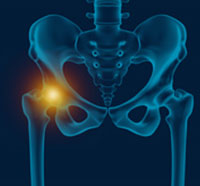

The hip joint is the largest weight-bearing joint in the human body. It is also referred to as a ball and socket joint and is surrounded by muscles, ligaments, and tendons. The thigh bone or femur and the pelvis join to form the hip joint.

The hip joint is a "ball and socket" joint. The "ball" is the head of the femur or thigh bone, and the "socket" is the cup-shaped acetabulum. The joint surface is covered by a smooth articular surface that allows pain-free movement in the joint.

The hip joint is one of the largest weight-bearing joints in the body, formed by the thigh bone or femur and the acetabulum of the pelvis. It is a ball and socket joint with the head of the femur as the ball and the pelvic acetabulum forming the socket.

The hip joint is one of the body's largest weight-bearing joints and is the point where the thigh bone (femur) and the pelvis (acetabulum) join. It is a ball and socket joint in which the head of the femur is the ball and the pelvic acetabulum forms the socket.